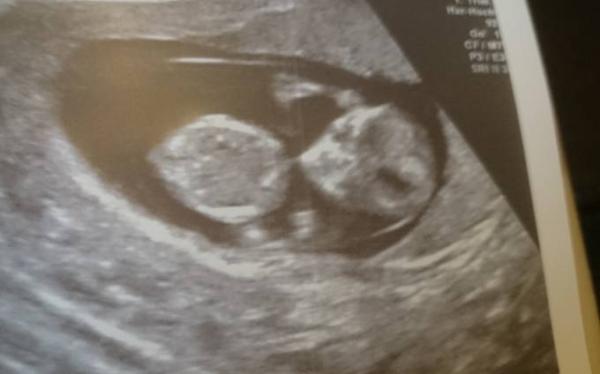

Zum Glück heute ein schöner Termin. Herzschlag und Bewegung nach wie vor da. Gute Zeitgerechte Entwicklung. Witziges Bild wo man zwar die Arme sieht (am Kopf) aber keine Beine ;-) Aber die waren auch da. Sonst ist mir weiterhin immer übel und ich hoffe drauf, dass es noch nachlässt.

Bild zu Zurück vom FA 11+3 - Forum für April - Mamis